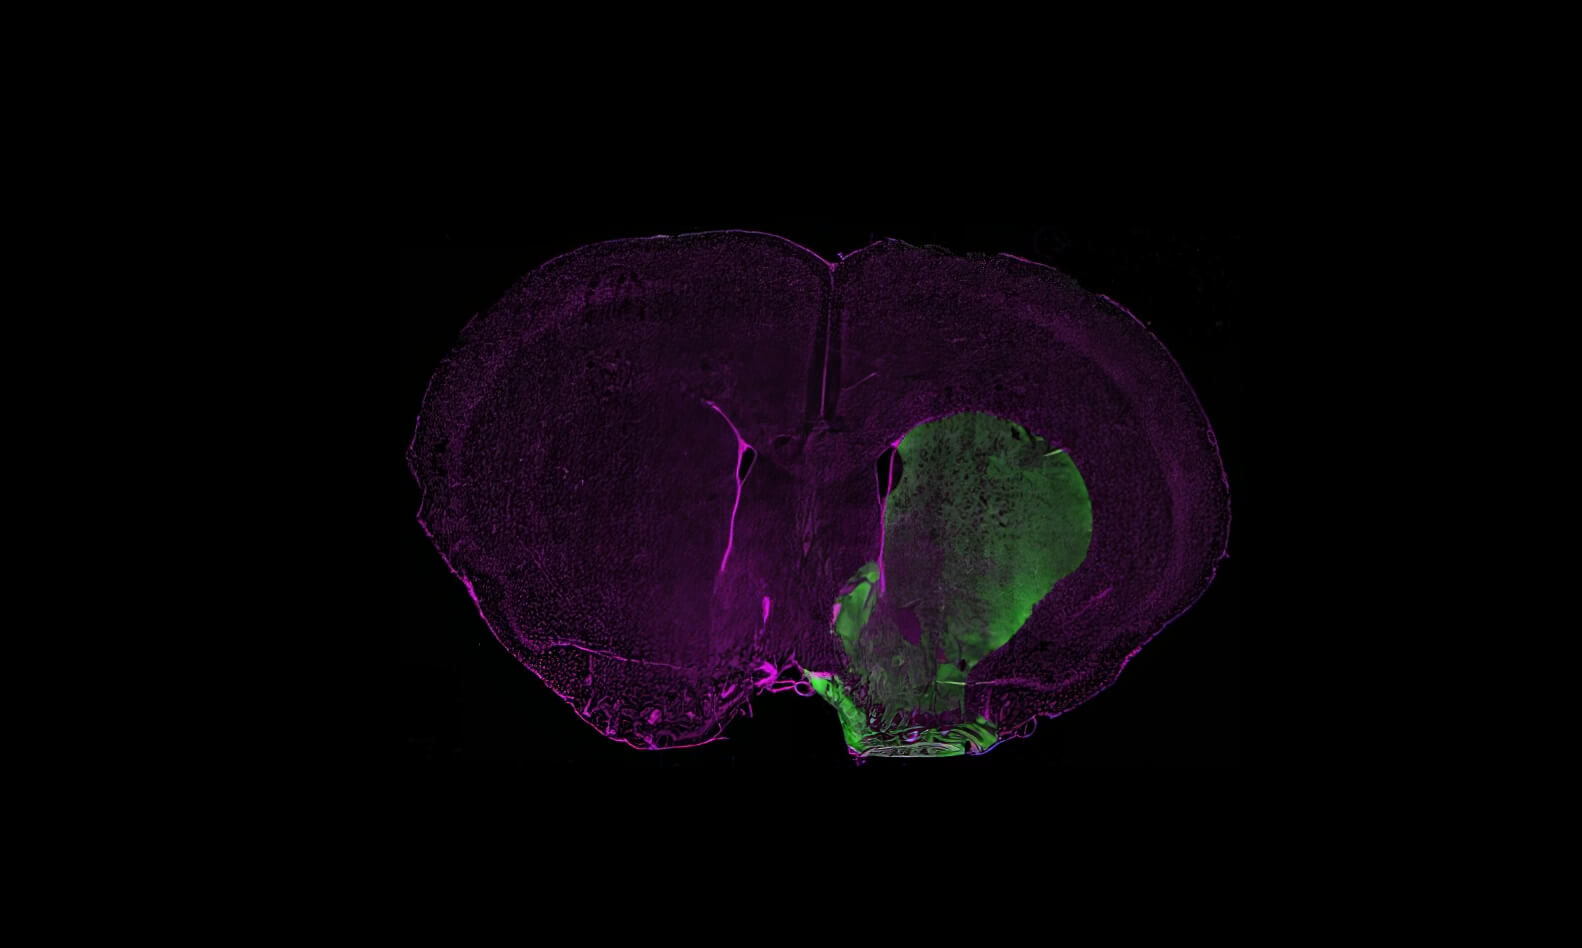

Dopaminergic neuron degeneration induced by intranigral injection of the neurotoxin 6-OHDA

The unilateral injection of 6‑OHDA specifically targets the SNpc, leading to an almost complete lesion of the nigrostriatal pathway. The lesioned animals exhibit motor impairments, including akinesia, a selective loss of dopaminergic neurons, and neuroinflammation.